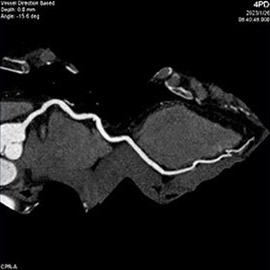

80列マルチスライスCTで撮影した画像

心臓(冠動脈)

主に狭心症や心筋梗塞などの診断